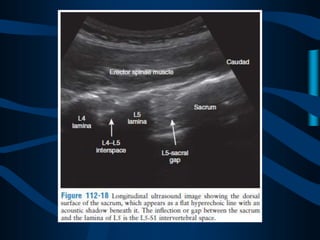

ABORDAJE

PARAESPINOSO

MEDIAL

ABORDAJE CLASICO

DE DOS AGUJAS